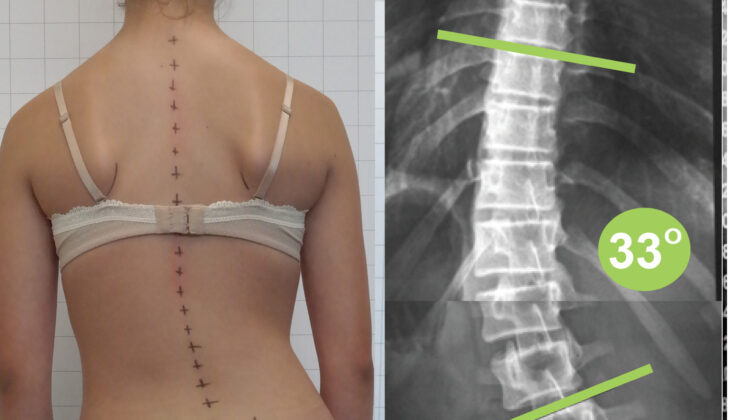

اعوجاج العمود الفقري القطني يعني وجود انحناء جانبي غير طبيعي في هذا الجزء من العمود الفقري، ويُقاس هذا الانحناء باستخدام الأشعة لتحديد درجته وشدته.

كيف يتم تشخيص اعوجاج العمود الفقري القطني؟

يعتمد التشخيص على مجموعة من الخطوات الأساسية، تشمل:

الفحص السريري ووضعية الجسم

تقييم مستوى الحوض والكتفين

الأشعة السينية لقياس زاوية الاعوجاج

هذه الخطوات تساعد الطبيب على اتخاذ القرار العلاجي الصحيح.